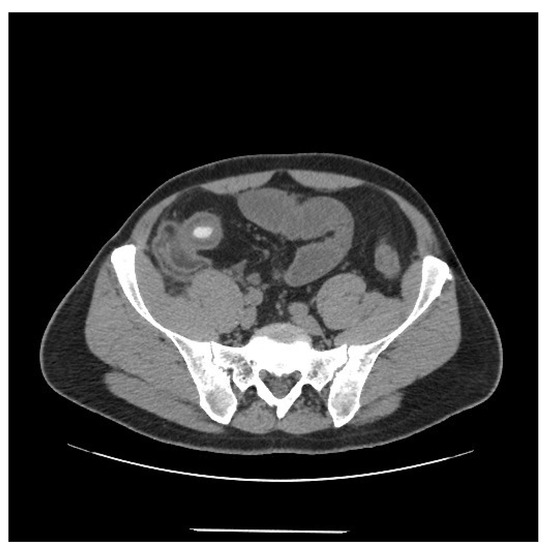

1.1. Case 1